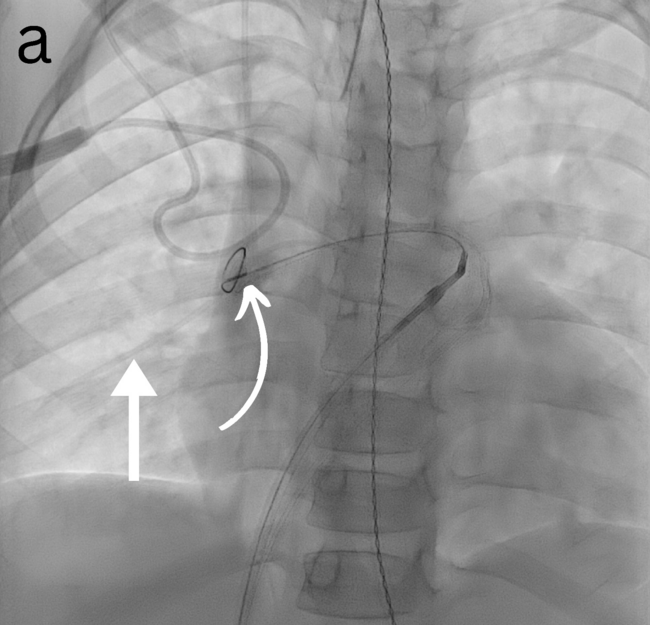

All the procedures were performed under general anesthesia. No prophylactic antibiotics were used for any procedures. Vascular access was obtained through the femoral veins. Ultrasound and fluoroscopy were the guidance modalities used in all (Figure). The retrieval sheath size ranged from 4 to 14 French (Fr). Various angled and reverse-angled catheters were used to reach the embolization site, with sizes ranging from 4 to 6 Fr. A snare was used to retrieve the foreign body in 8 cases, while a combination of snare, aspiration catheter, and suction device was used in 1 case. A single-loop snare device was used in all patients but one, in which a combination of single and tri-loop snare devices was used. The loop sizes of snare devices ranged from 6 to 25 mm. Hemostasis was achieved by compression in all cases. Heparin was not used for any of the cases.

Nine patients with a mean age of 8.56 years (SD = ± 4.25 years; range, 4-17 years) were included (Table). There were 5 male and 4 female patients. We observed an equal number of cases with embolized foreign bodies in the main, left, and right pulmonary arteries (3 cases each). Foreign bodies were present for 1 day from the day of identification in 6 patients, while 3 patients had foreign bodies in place for 2, 14, and 27 days, respectively. The most common type of foreign body was a port catheter (55.6%, n = 5), followed by a central line, a peripherally inserted central catheter (PICC), coils, and N-butyl cyanoacrylate (n-BCA) glue with Lipiodol (1 case each). All (n = 5) port catheters were initially placed in the subclavian vein. Of these 5 port catheters, 4 dysfunctioned after an average of 3.2 years (SD = 1.3; range, 1.2-4.2), while 1 dysfunctioned 15 days after placement. Catheter fracture was the most common (77.8%, n=7) cause of foreign body. Most (n = 5) catheters fractured spontaneously, while 2 fractured during attempted removal. The foreign body was identified using a plain radiograph in most cases (66.7%, n = 6), followed by fluoroscopy and angiography during the procedure (11.1%, n = 1 each). The foreign bodies were successfully retrieved in all cases. In the case of the embolized coils, a femoral cutdown was also required to remove the coil mass safely.

In one of our cases, n-BCA glue mixed with Lipiodol embolized from the iliac veins to the pulmonary arteries. Stable access was established via 10- and 12-Fr Check-Flo sheaths (Cook Medical) inserted through the popliteal and femoral veins to prevent further migration. Negative pressure aspiration was initially employed to remove the glue from the femoral and iliac veins. For fragments that had traveled to the pulmonary arteries, gooseneck snares were utilized to carefully retrieve the embolized material. An aspiration catheter (Penumbra, Inc.) was employed for more resistant fragments, enabling precise and focused suction directly within the pulmonary arteries. This combination of techniques ensured the effective and safe removal of the foreign body. The estimated blood loss was 300 mL. There were no immediate complications except transient arrhythmias during 1 procedure while maneuvering the catheter across the right atrium, which resolved independently.